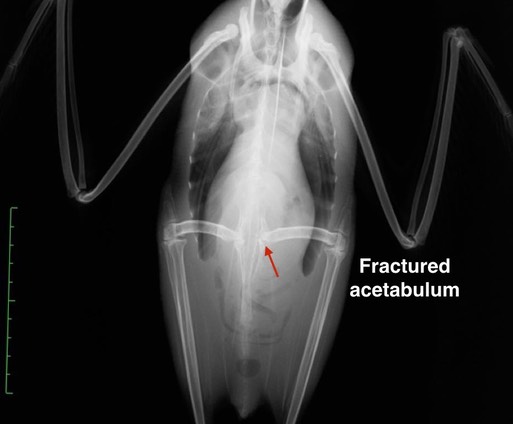

Western Grebe 18-664

Fall is the time of year when we occasionally admit grebes. They mistake wet pavement or a large puddle for a larger body of water and crash land. Even if they are uninjured, they are unable to take off because they need to run across the water in order to get air born. This Western Grebe did injure itself, fracturing the left acetabulum (hip socket). Fortunately he is being a cooperative patient and eating very well. After about two weeks of cage rest we will begin swimming therapy. Hopefully he/she will be ready for release soon.